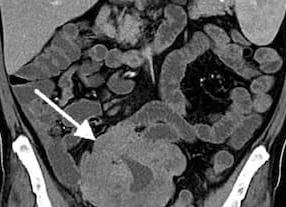

Снимок кишечника при проведении гидро МРТ. Стрелка указывает на гемангиому.

Однако МРТ не может справиться с особенностью анатомического строения этого отдела пищеварительного тракта. В первую очередь, на магнито-резонансной томографии не видны кишечные , наслаивающиеся друг на друга.